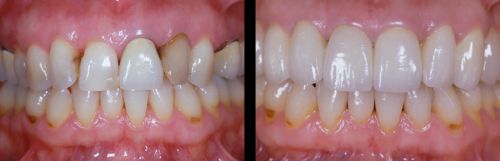

Consultatie+detartraj+periaj+airflow la numai 50RON

Va oferim un pachet de consultatie, plan de tratament, detartraj,periaj profesional si airflow la numai 50 RON in loc de 150 RON. Oferta de albire dentara este valabila numai luna Aprilie. Pentru detalii va rugam sa sunati la numarul de telefon...